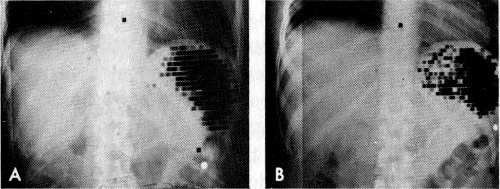

Spleen scans made with red blood cells, which had been altered by heat treatment and tagged with chromium-51. Such damaged cells are selectively removed by the spleen. A is a normal spleen. B shows an abscess in the spleen. Note dark ring of radioactivity surrounding the lighter area of decreased activity at the central portion of spleen.